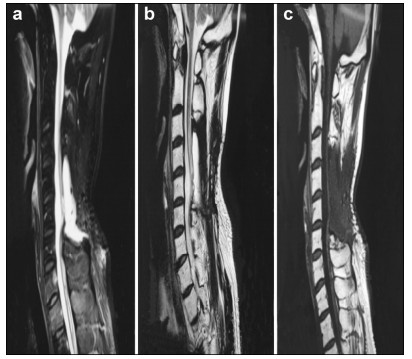

A 46-year-old male presented with a 4-year history of upper and lower limb numbness and weakness (motor strength 4/5 and 2/5 in upper and lower limbs, respectively). Symptoms worsened 30 days before consulting our facility. Magnetic resonance imaging (MRI) of the spinal cord showed an intramedullary mass at C5-C6. Surgical resection under awake anesthesia was recommended; the patient received detailed information regarding the procedure and possible risks, and informed consent was obtained. He remained intubated and his motor speech function was not monitored, because the language center was not involved in surgery. The patient followed commands and performed all upper and lower limb movements as instructed. Sensory functions were not fully assessed; instead, minimal monitoring was performed with sensory stimulation of his hands and feet, with instruction to raise his thumb if he perceived sensation. GTR of the tumor was performed under awake (AAA) anesthesia with neurophysiological monitoring (NPM). Intraoperative frozen section confirmed the diagnosis of diffuse spinal cord astrocytoma. Symptoms completely resolved postoperatively, and no motor deficits were observed; however, there was minimal numbness in the finger tips.

Preoperative and postoperative MR images of Case 1 are shown in Figure 1 and Figure 2, respectively.

| Figure 1 a–c. Preoperative MR images of Case 1. |